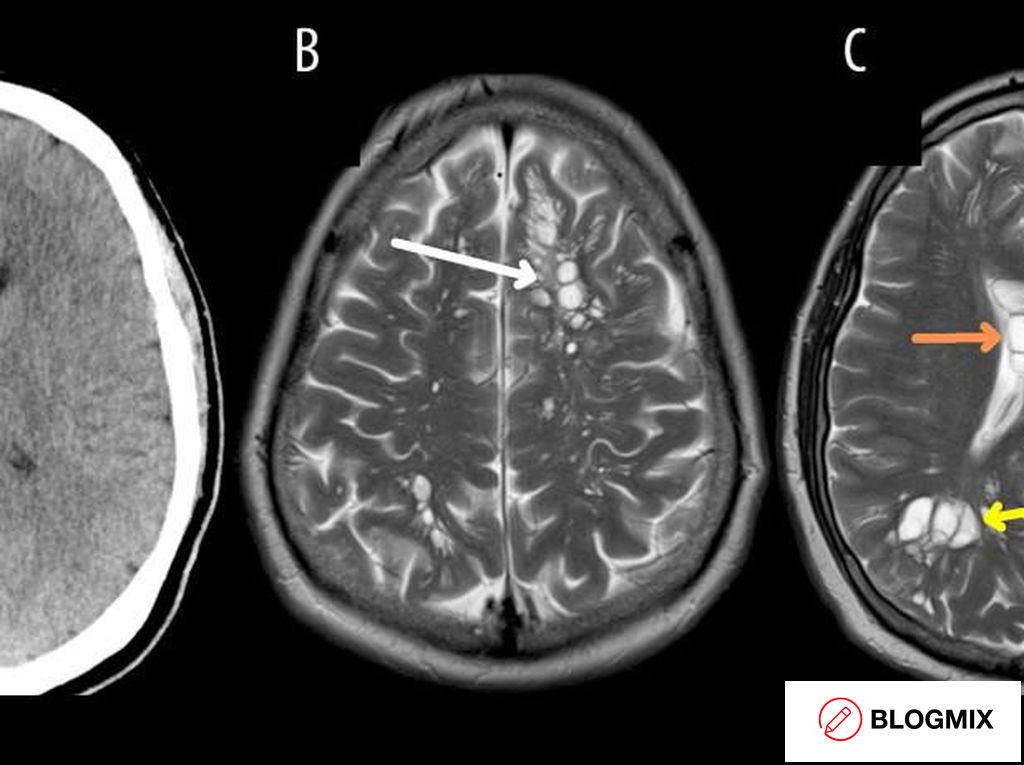

Merinding! Sederet Kasus Cacing Pita Bersarang di Tubuh Manusia, Perut hingga Otak

keberadaan cacing pita di dalam tubuh dapat merusak kesehatan organ infeksi ini bisa terjadi akibat kebiasaan yang kurang sehat seperti mengonsumsi daging yang...